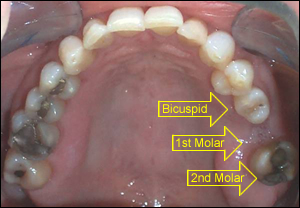

Fig 1: A 45 year old female presented with a unique problem in her upper left sextant. The 1st molar was lost to periodontal disease but could not be replaced with a dental implant due to insufficient bone and a very low sinus. A 3-unit fixed bridge was considered, but the 2nd molar proved to be an inadequate abutment because it was mobile. The rotated bicuspid was healthy.